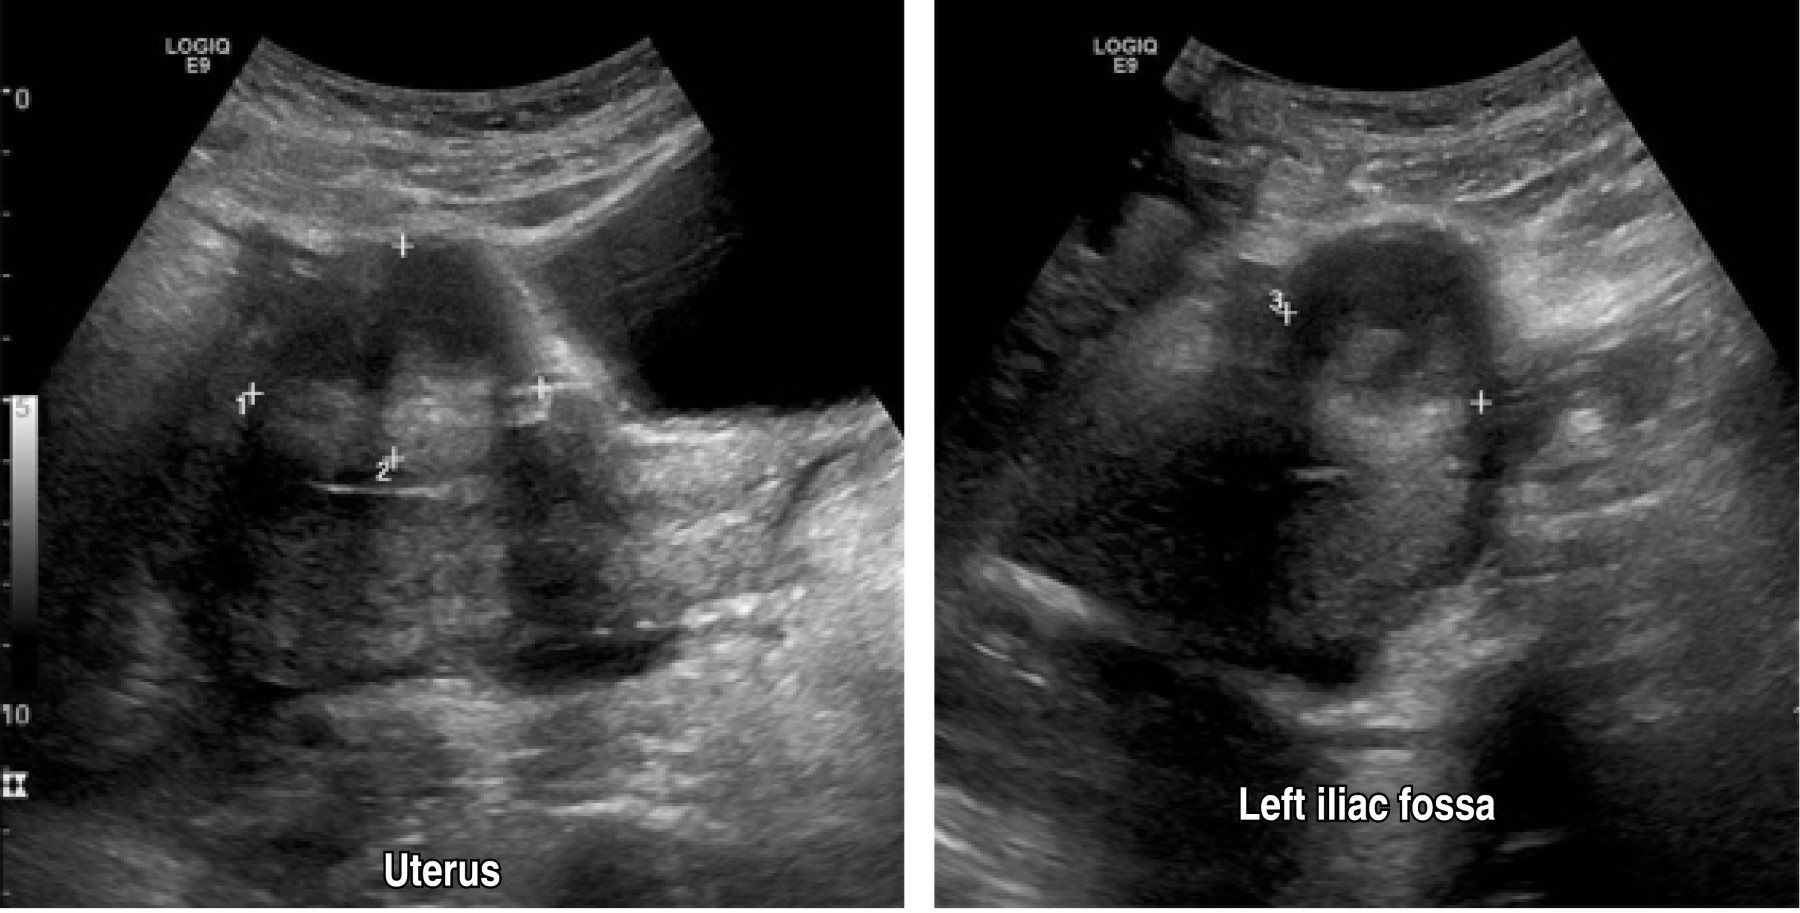

A 40-year-old female patient had four gestations, three deliveries, and a history of aortic valve stenosis since 2017 with surgical management based on valve prosthesis placement and use of acenocoumarin until the diagnosis of her last pregnancy, during which oral the anticoagulant drug was suspended, and enoxaparin was started. She started her current condition when she was admitted to the obstetrics service with a gestational age report of 28.5 weeks of gestation (SDG) by the last menstrual period and 29.4 by fetometry. Preeclampsia was diagnosed with severe data, so it was decided to perform a Kerr cesarean section and bilateral tubal occlusion with Kroener technique, reporting 350 cm3 of bleeding, obtaining a single live male product of 31.5 weeks by Capurro, with an Apgar score of 7/8, and with cleft lip and palate. She was discharged on the fifth day, requiring a transfusion of blood products in her immediate postoperative period. Twenty-one days later, she was readmitted due to abundant and fetid bleeding through the surgical approach; wound healing was performed, and an abdominal wall defect was evidenced, so it was decided to perform an ultrasound, with findings of a defect in the anterior abdominal wall in the cephalic portion of the wound through which intestinal loops protrude (Figures 1 and 2). In an abdominal computerized tomography scan, a heterogeneous non-measurable collection was identified in the middle and caudal third of the wound at the level of the subcutaneous plane, as well as a thick-walled collection in the pelvic cavity and left iliac fossa (Figure 3).

Figure 2